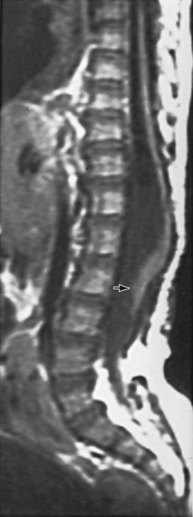

In addition to MRI studies (Tracey and Hanigan, 1990), urodynamic testing including EMG of the external urethral sphincter should be performed in every child who has a questionable cutaneous or bony abnormality of the lower spine, especially if there is a radiologic abnormality of the spinal cord (Packer et al, 1986; Campobasso et al, 1988; Hall et al, 1988; Meyrat et al, 2003). This test provides the most accurate measure of sacral spinal cord function at diagnosis and provides a basis for comparison with subsequent studies when the children are either operated on or carefully observed. In children younger than 3 months of age the vertebral bones have not ossified; thus a window of opportunity exists for ultrasonography to be a useful screening tool in visualizing the spinal canal (Fig. 128–15) (Raghavendra et al, 1983; Scheible et al, 1983). At this age there is good correlation between the ultrasound imaging and MRI findings; however, if a spinal cord abnormality is identified the latter provides for a better definition of the spinal cord lesion. Consequently, ultrasonography should not be used as the definitive imaging modality (Hughes et al, 2003). Older children with an occult spinal cord lesion may have urologic symptoms in 20% of cases (Hsieh et al, 2006), and 50% to 60% may have abnormal urodynamic findings preoperatively (Geurra et al, 2006). Resolution of the abnormal urodynamic parameters is noted in 50% to 60% of cases after detethering (Hseih et al, 2006; Geurra et al, 2006). Therefore, urodynamic study is recommended for all children with an occult spinal dysraphism before and after spinal cord detethering procedures.

Figure 128–15 A, During the first few months of life, ultrasonography can clearly demonstrate intravertebral anatomy because the posterior arches have not completely ossified. Note that the spinal cord along with its central canal is displaced anteriorly (white arrows) beginning at L3 because of an intradural lipoma. B, The MR image is juxtaposed to confirm the ultrasound findings. The longitudinal white intraspinal mass (black arrows) is the lipoma; the longitudinal gray mass is the spinal cord.